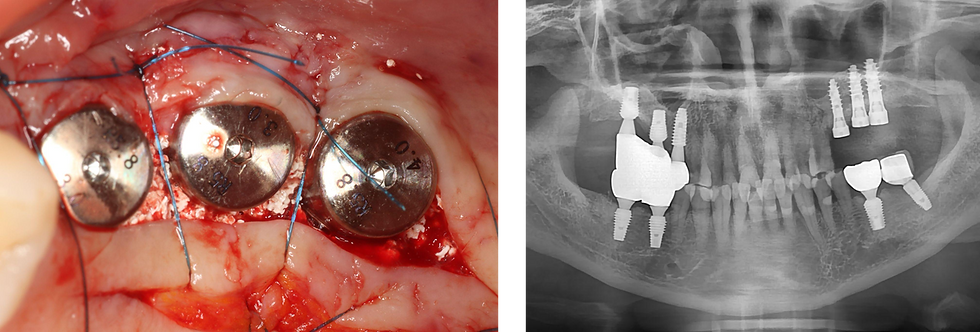

ALX-IT fixtures were placed. #25 - ALX-IT 4.5 x 10mm, cuff 4mm, D221, 40N/cm

#26 - ALX-IT 5.0 x 10mm, cuff 5mm, D332, 30N/cm

#27 - ALX-IT 5.0 x 10mm, cuff 5mm , D332, 30N/cm

After implant placement, bone grafting was performed around the exposed threads and between the fixtures to enhance bone volume and achieve stable ridge contour

After placement of all 3 fixtures and bone graft material, suture was done

Post-op panoramic radiograph showing the placement of 3 ALX fixtures with ideal positioning and parallelism